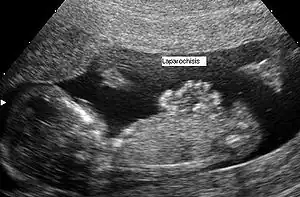

Dépistage prénatal échographique (vue sagittale)

Laparochisis à 12 semaines. Vue sagittale.

Le diagnostic anténatal est possible par échographie. La paroi abdominale ne se fermant complètement qu’à 12 semaines, le diagnostic de laparoschisis ne peut être fait avant cette période.